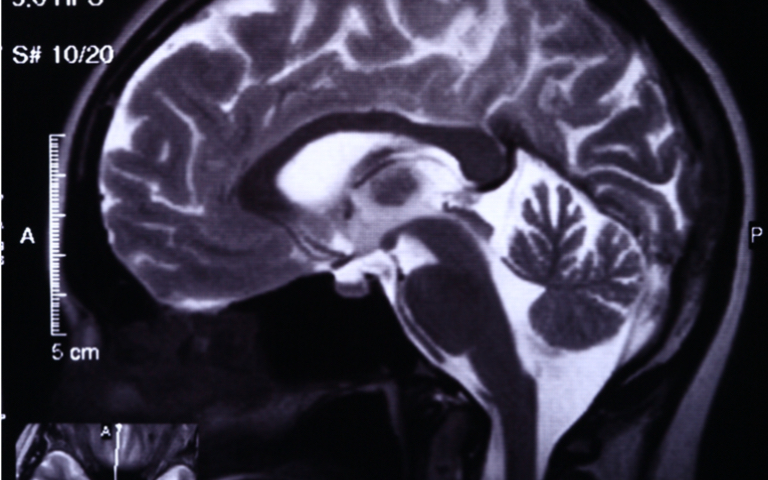

Das Analystenteam von CybelAngel, dem Spezialisten für digitales Risikomanagement, stellt jetzt seinen aktuellen Forschungsbericht „Full Body Exposure“ vor. Demnach sind im Internet weltweit mehr als 45 Millionen medizinische Bilddateien – darunter Röntgen-, CT- und MRT-Scans – auf ungeschützten Servern für jedermann frei zugänglich.

Der Bericht „Full Body Exposure“ basiert auf Untersuchungen von Network Attached Storage (NAS) und Digital Imaging and Communications in Medicine (DICOM), die über sechs Monate hinweg weltweit durchgeführt wurde. DICOM ist der De-facto-Standard, den Mediziner zum Senden und Empfangen medizinischer Daten verwenden. Die Analysten deckten im Rahmen ihrer Recherche auf, dass Millionen sensibler Bilder und Patientendaten im Internet frei zugänglich sind – unverschlüsselt und ohne Passwortschutz.

Für den Bericht scannten die CybelAngel-Tools auf mehr als 2.140 Servern rund 4,3 Milliarden IP-Adressen in 67 Ländern. Dabei wurden mehr als 45 Millionen medizinische Bilder identifiziert, die für jedermann offen zugänglich waren. Allein in Deutschland fanden die Analysten in den letzten sechs Monaten auf 251 Servern 39.204 frei zugängliche DICOM-Aufnahmen. In Großbritannien wurden im gleichen Zeitraum auf 90 Servern 23.238 solcher Bilder entdeckt. Die medizinischen Aufnahmen enthielten bis zu 200 Zeilen Metadaten mit persönlichen Informationen, die eine zweifelsfreie Identifizierung der betroffenen Patienten ermöglichte. Die Daten ließen sich aus allen identifizierten Quellen problemlos ohne Benutzernamen oder Passwort abrufen. In einigen Fällen akzeptierten Login-Portale auch leere Benutzernamen und Passwörter.